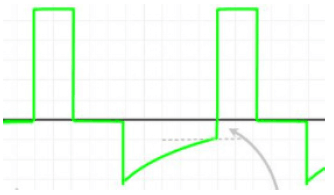

Paciente de 25 anos do sexo feminino com antecedente de asma dá entrada no pronto-socorro em franca crise de broncoespasmo e insuficiência respiratória, não respondendo às medidas para controle da doença de base. Como consequência, é intubada.

À ventilação mecânica, após ajustados os parâmetros iniciais, observa-se, em modo volume controlado, a seguinte curva de fluxo x tempo:

Para amenizar o fenômeno apontado pela seta, todas as condutas abaixo são plausíveis, à exceção de uma. Assinale-a.